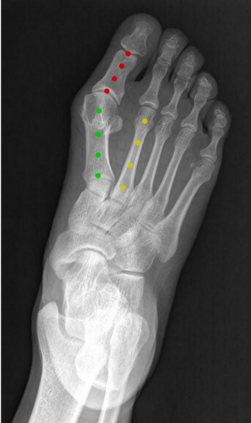

Angular measurements is essential to make a resonable treatment for Hallux valgus (HV), a common forefoot deformity. However, it still depends on manual labeling and measurement, which is time-consuming and sometimes unreliable. Automating this process is a thing of concern. However, it lack of dataset and the keypoints based method which made a great success in pose estimation is not suitable for this field.To solve the problems, we made a dataset and developed an algorithm based on deep learning and linear regression. It shows great fitting ability to the ground truth.